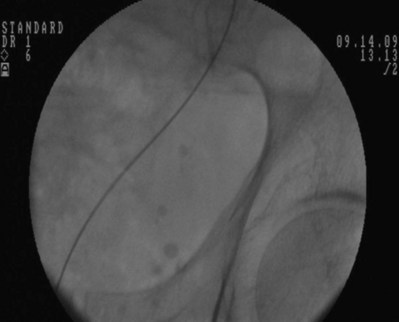

Figure 7–13 A metal tip pusher is used to advance the stent to the desired position. Asterisk shows the pushers radiopaque marker.

The ureteral stent is then advanced over the guidewire through the 10-Fr sheath by using a pusher with a small fluoroscopically visible metal band at its tip. The metal tip pusher is advanced under fluoroscopic control to the upper border of the pubic symphysis in male patients and lower border in female patients, while stabilizing the position of the lower end of the stent. The 10-Fr sheath and subsequently the guidewire are removed, allowing the stent to curl in the bladder.